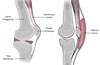

Where is the subacromial bursa located?

Between the acromion and the rotator cuff